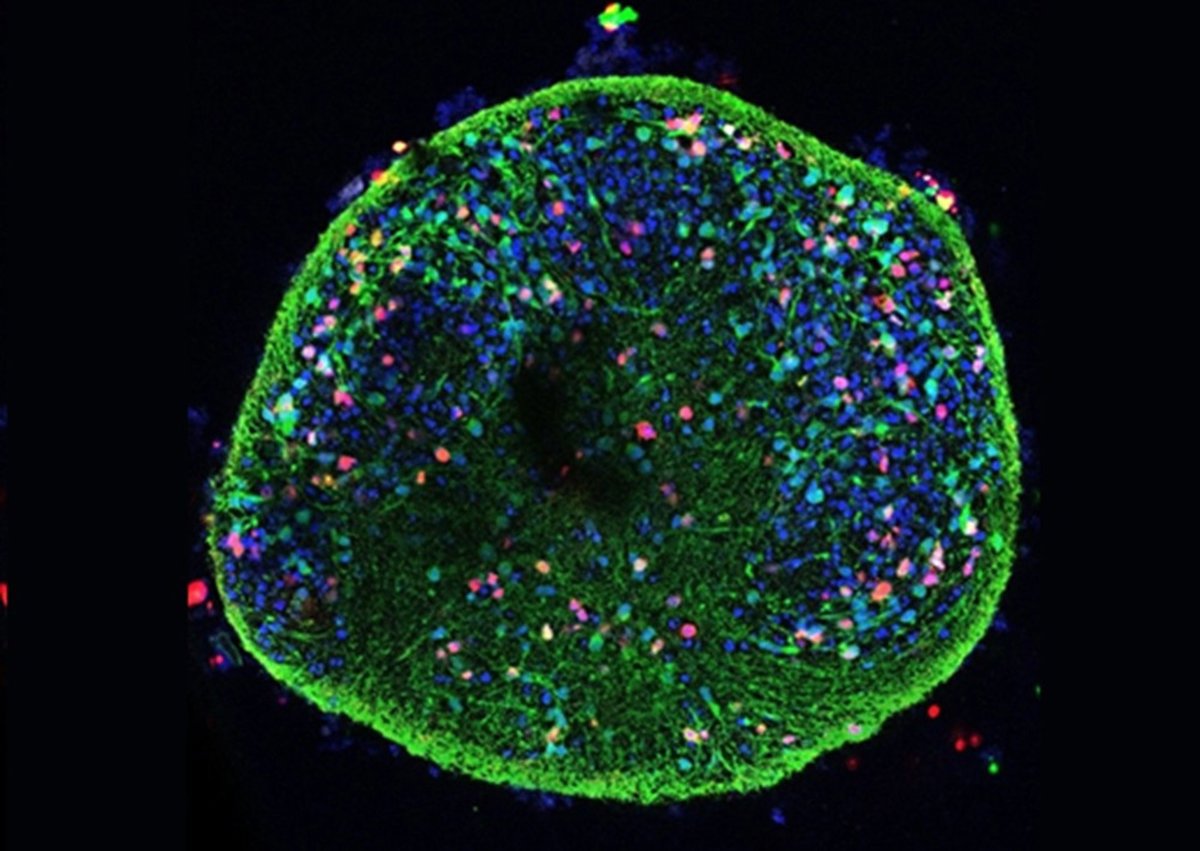

"Estos modelos tridimensionales permiten que las células crezcan formando agregados que imitan mejor la organización del tejido nervioso humano, reproduciendo, de forma más realista, las interacciones y el entorno que existen en el cerebro", ha detallado Jesús Aldudo, quien también es miembro del CBM. Así, estos modelos se han organizado en forma de pequeñas esferas (esferoides) porque, en el entorno 3D, las neuronas pueden crecer en todas direcciones, forman redes más complejas y se estructuran en capas, algo más aproximado a lo que ocurre en el tejido cerebral, que no permiten los cultivos planos tradicionales

Este trabajo indica que el virus del herpes labial interfiere en un sistema fundamental de limpieza celular encargado de degradar y reciclar proteínas dañadas o innecesarias, ya que, cuando este mecanismo falla, las proteínas alteradas se acumulan y se pueden favorecer procesos de neurodegeneración. Este es, a juicio de los investigadores, un descubrimiento sumamente relevante, ya que estos efectos no solo se detectaron en cultivos celulares simples, sino también en modelos tridimensionales, donde el virus fue capaz de penetrar en toda la estructura neuronal y provocar las mismas alteraciones moleculares relacionadas con el Alzheimer.